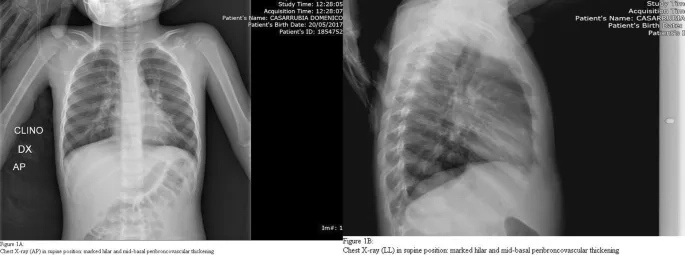

• Respiratory symptoms like a dry cough, shortness of breath, and chest pain can develop, potentially leading to pneumonia if untreated.